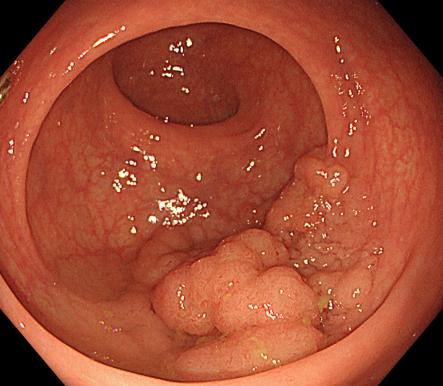

直腸側向發育性腫瘤 內鏡下黏膜下剝離術后創面

內鏡下黏膜剝離術(ESD):治療巨大平坦息肉,早期癌及癌前病變,黏膜下腫瘤等。